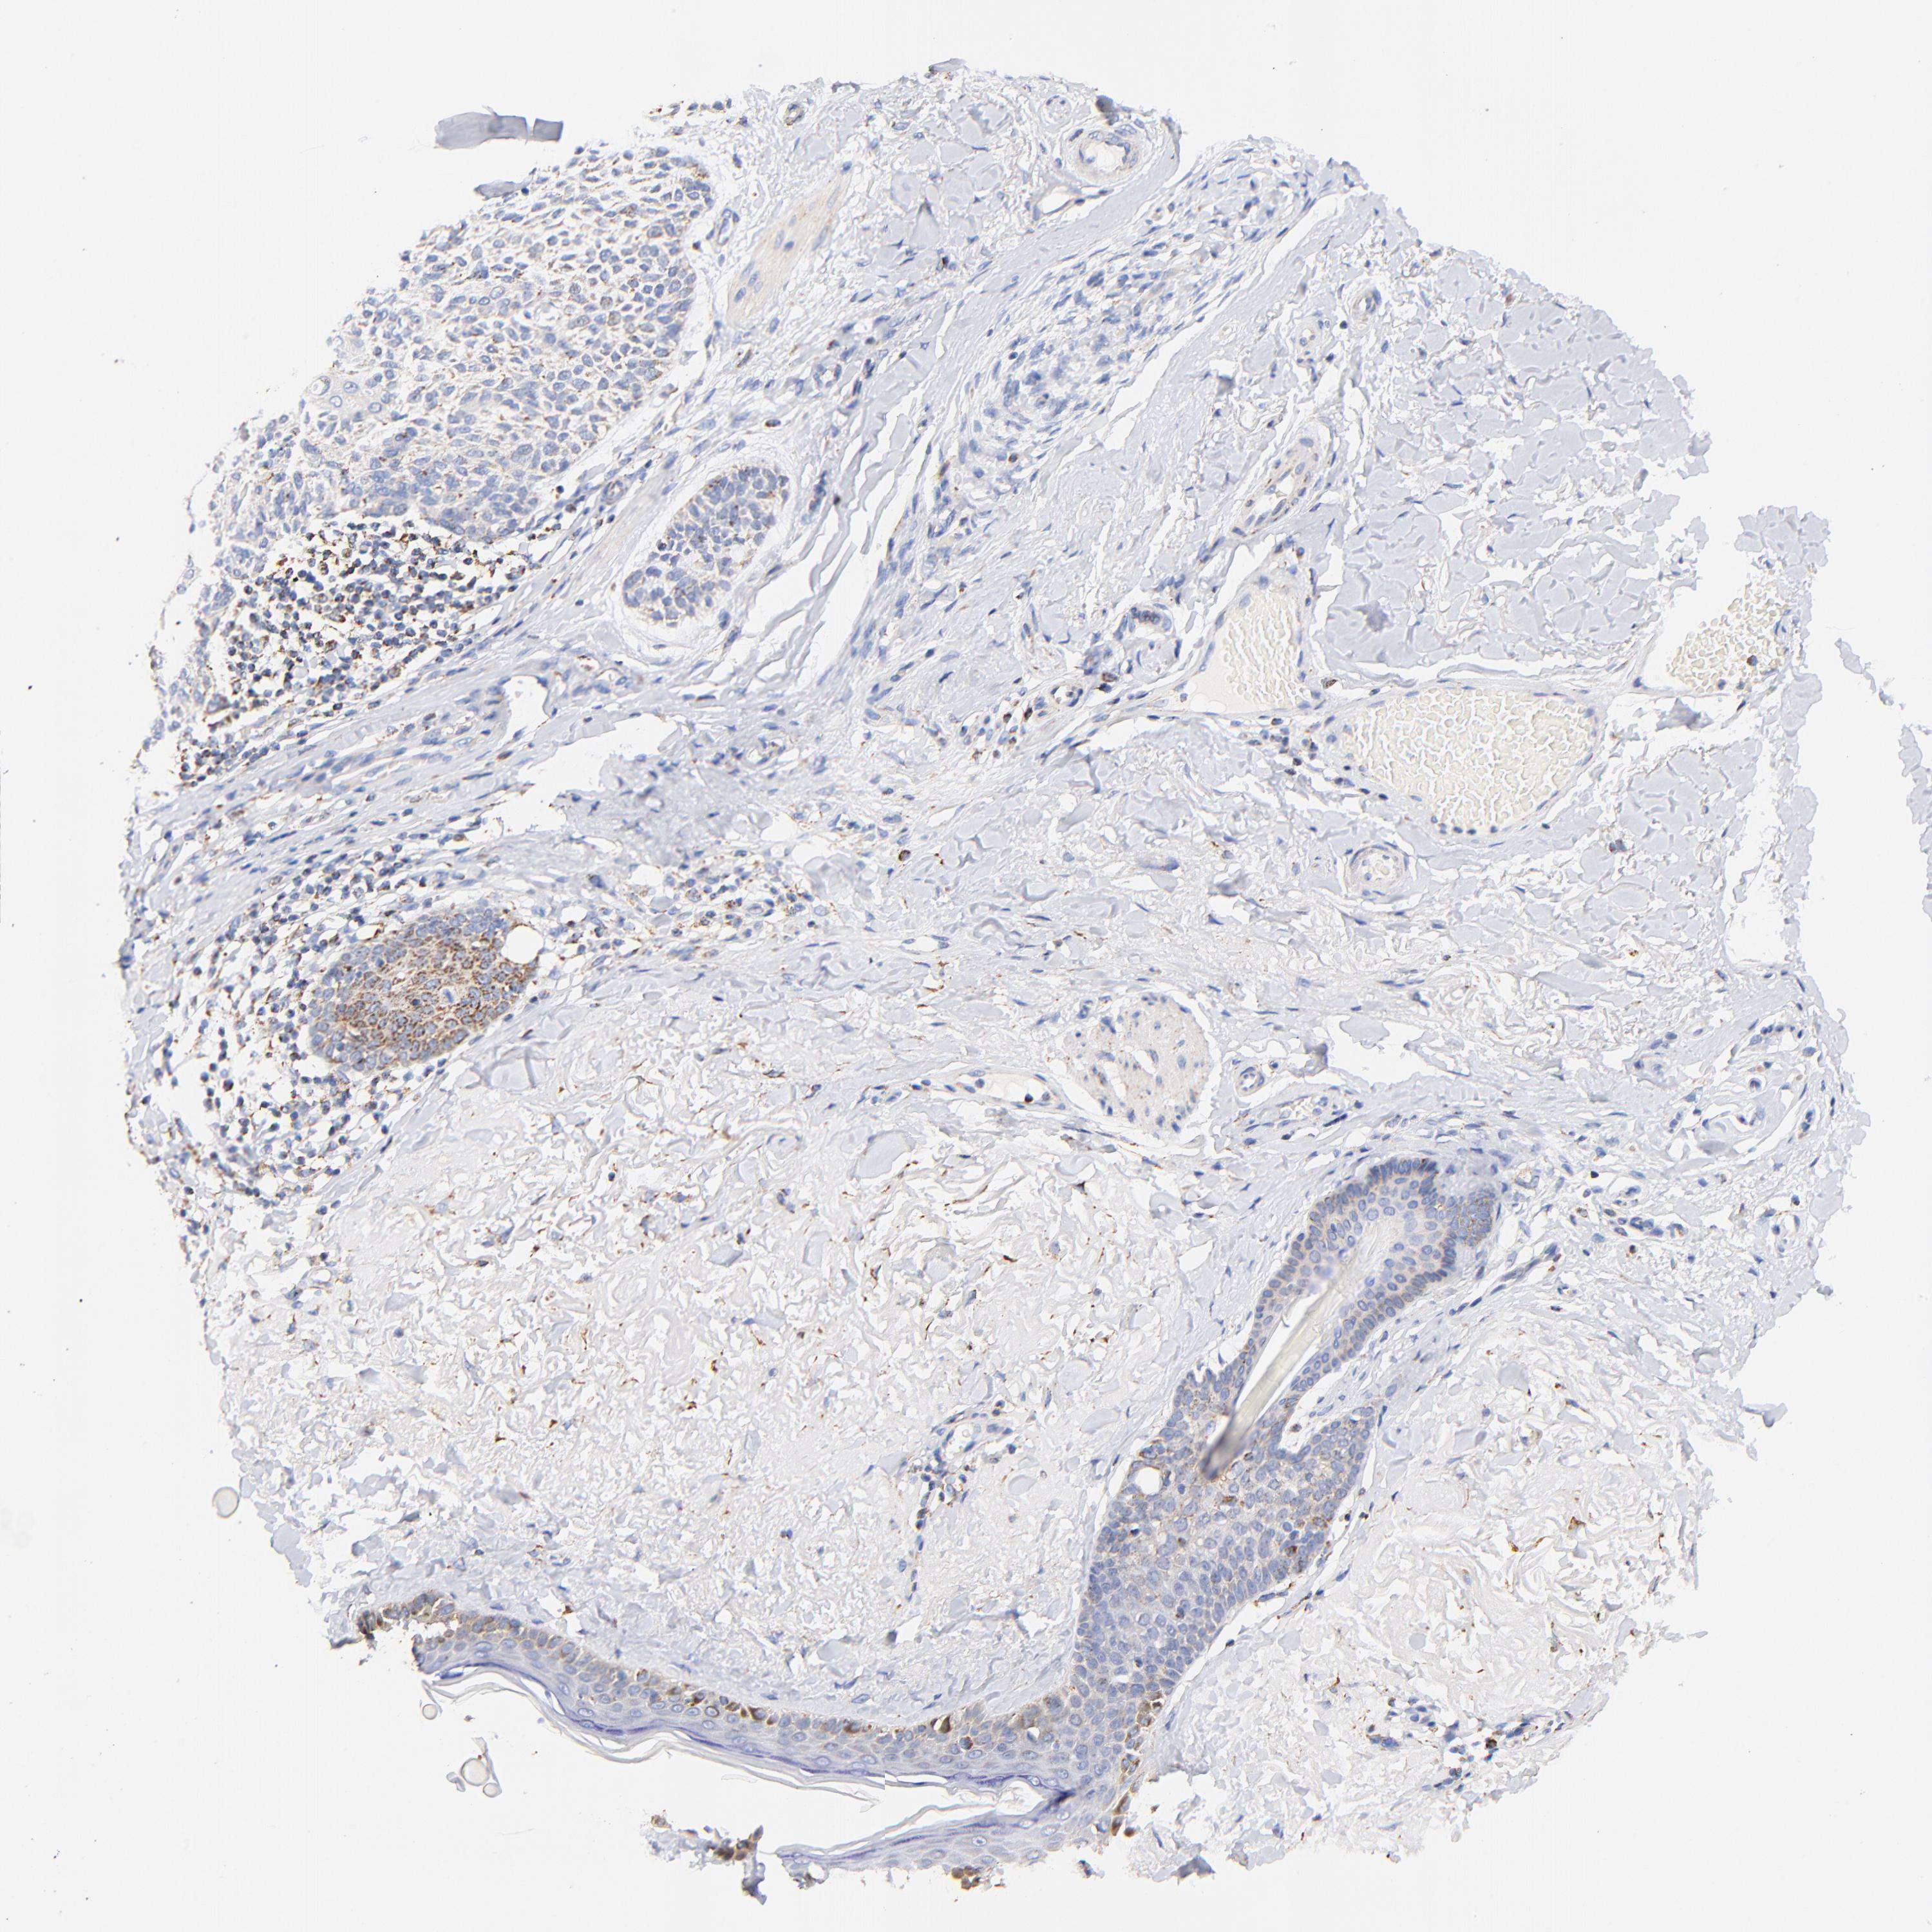

Basal cell and squamous cell cancer

SKIN CANCER - Protein expressioni

A mouse-over function shows sample information and annotation data. Click on an image to view it in a full screen mode. Samples can be filtered based on level of antibody staining by selecting one or several of the following categories: high, medium, low and not detected. The assay and annotation is described here.

Antibody stainingi

Antibody staining in the annotated cell types in the current human tissue is reported as not detected, low, medium, or high, based on conventional immunohistochemistry profiling in selected tissues. This score is based on the combination of the staining intensity and fraction of stained cells.

Each image is clickable and will lead to virtual microscopy that enables deeper exploration of all samples and also displays staining intensity scores, fraction scores and subcellular localization as well as patient and tissue information for each sample.

Antibody HPA002865

Staining

High

Medium

Low

Not detected

Intensity

Strong

Moderate

Weak

Negative

Quantity

>75%

75%-25%

<25%

None

Location

Nuclear

Cytoplasmic/membranous

Cytoplasmic/membranous,nuclear

Squamous cell carcinoma, NOS

Basal cell carcinoma